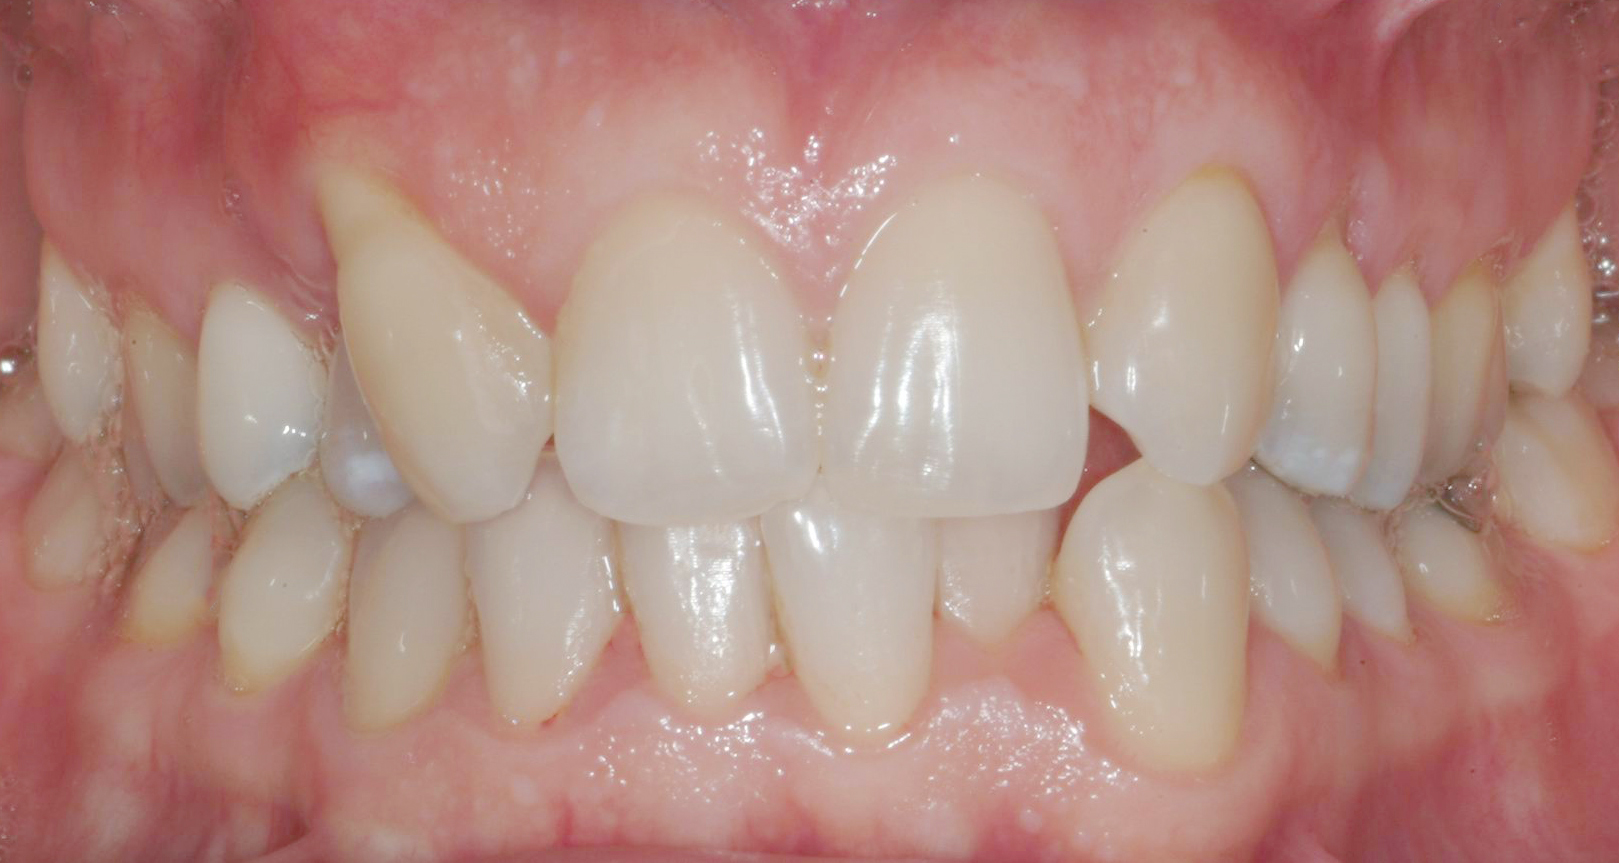

Una paziente di sesso femminile, 38 anni, già trattata ortodonticamente presso altra sede con apparecchiatura fissa a entrambe le arcate in età adolescenziale senza successiva applicazione di alcuna contenzione, si presenta alla nostra attenzione perché insoddisfatta dell’estetica del sorriso; richiede una valutazione per un trattamento ortodontico con apparecchiatura fissa linguale per la presenza di affollamento dentale a entrambe le arcate e difficoltà a mantenere una adeguata igiene orale; si riscontrano agenesia di entrambi gli incisivi laterali superiori (1.2 e 2.2) e del secondo premolare inferiore destro (4.5). Presentiamo la risoluzione del caso mediante trattamento ortodontico estrattivo a entrambe le arcate, eseguito con apparecchiatura linguale invisibile 2D e meccanica asimmetrica e seguito a medio termine da riabilitazione implanto-protesica e contenzione fissa.

Per formulare corretta diagnosi e piano di cura, lo studio del caso ha previsto la raccolta di documentazione completa standard, ovvero fotografie del viso e intraorali (Figure 1a-e), radiografia panoramica e teleradiografia del cranio in proiezione laterale (Figure 2a-b) per la relativa analisi cefalometrica e modelli di studio.

La valutazione clinica e gli esami effettuati confermano la presenza di agenesia degli incisivi laterali superiori (1.2 e 2.2) e del secondo premolare inferiore destro (4.5).

L’analisi ortodontica e la valutazione parodontale, con particolare riferimento alla posizione della radice del canino superiore destro (1.3), distoinclinata e trasposta alla radice del primo premolare (1.4) come evidente dalla radiografia panoramica e dalle immagini intraorali, ci hanno guidati nella programmazione di un trattamento estrattivo asimmetrico a entrambe le arcate.